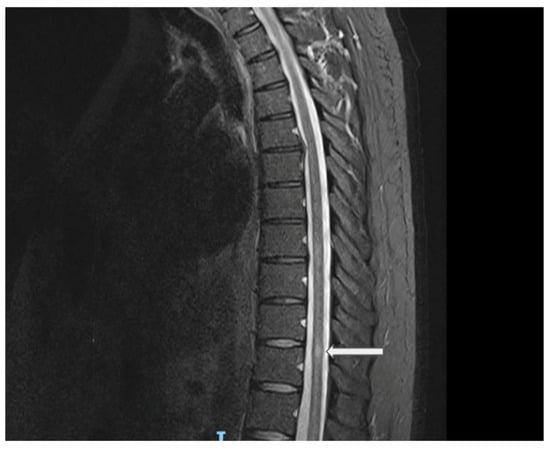

In August 2021, the patient presented with a 10-day history of ascending lower-limb numbness in both legs with some bladder urgency, without weakness or gait disturbance. Neurological examination showed preserved strength and reflexes with sensory impairment to the knees bilaterally; at that time, the estimated expanded disability status scale (EDSS) was 2.5. The brain MRI demonstrated no demyelinating lesions. The spine MRI revealed a small T2-hyperintense lesion at T11 with subtle cord expansion, minimal post-contrast enhancement, and a questionable ill-defined lesion at T8 (Figure 2). These findings were consistent with acute transverse myelitis. Serum AQP4 and MOG antibodies were again negative. CSF was positive for five unique OCBs. An extended diagnostic workup was performed to exclude alternative etiologies of myelitis, including ANA, ENA, ANCA, ACE, B12/MMA, infectious serologies (HIV, VZV, syphilis, TB), and paraneoplastic screening, all of which were unremarkable. He was treated with intravenous corticosteroids with good improvement. After this episode, the patient was diagnosed with LHON plus a demyelinating disease, most likely LHON-MS or Harding’s disease.

Figure 2. Sagittal spine MRI (STIR sequence) showing a central thoracic cord lesion with high T2 signal intensity opposite the superior aspect of the T11 vertebral level, associated with subtle cord expansion. Explanation of the arrow figure: central thoracic cord lesion with high T2 signal intensity opposite the superior aspect of the T11 vertebral level.